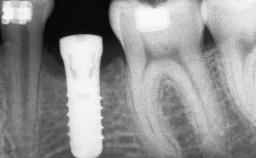

A 20-year-old woman was referred for implant therapy in 2004. Her medical history revealed no significant findings, and neither did she smoke nor take any medications. An extraoral examination revealed no abnormalities of the skin, hair or nails. The intraoral examination revealed only 11 permanent teeth clinically. These were normal in shape, size, and color. In addition, eight retained deciduous teeth (53, 62, 63, 71, 72, 73, 81, 82) were present. No abnormalities were detected during the general examination. The family history revealed that the patient’s father and two sisters were on record with similar conditions. The clinical examination revealed a thick gingival biotype. No recession of the attached gingiva was noted, but the retained deciduous teeth were mobile and unsightly. As a syndrome had not been diagnosed, the case was categorized as non-syndromic oligodontia.

# of Implants 12

Type of Implants One-Piece|Reduced-Diameter

Bone Augmentation Horizontal|Staged

Augmentation Materials Autogenous chips|Autogenous block(s)|Membrane